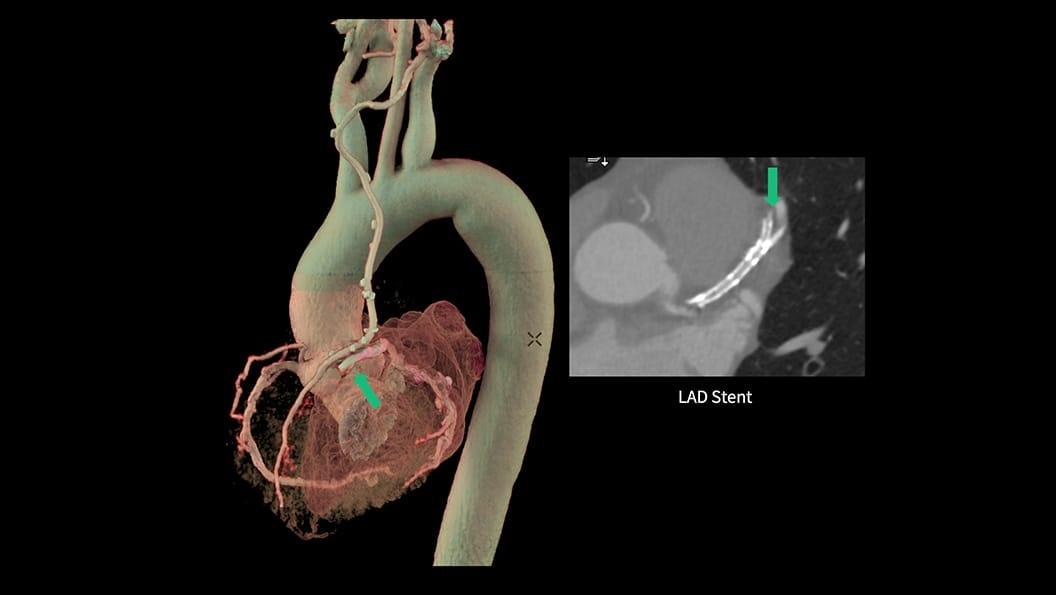

CT-Guided Interventional Care

Since becoming an important step in the patient care pathway and heart care guidelines, CT images are an invaluable tool in the cath lab, guiding procedures for precise personalized care.

CardiQ Suite

An integrated suite of CT Cardiac post-processing tools, built for automation and workflow efficiency.